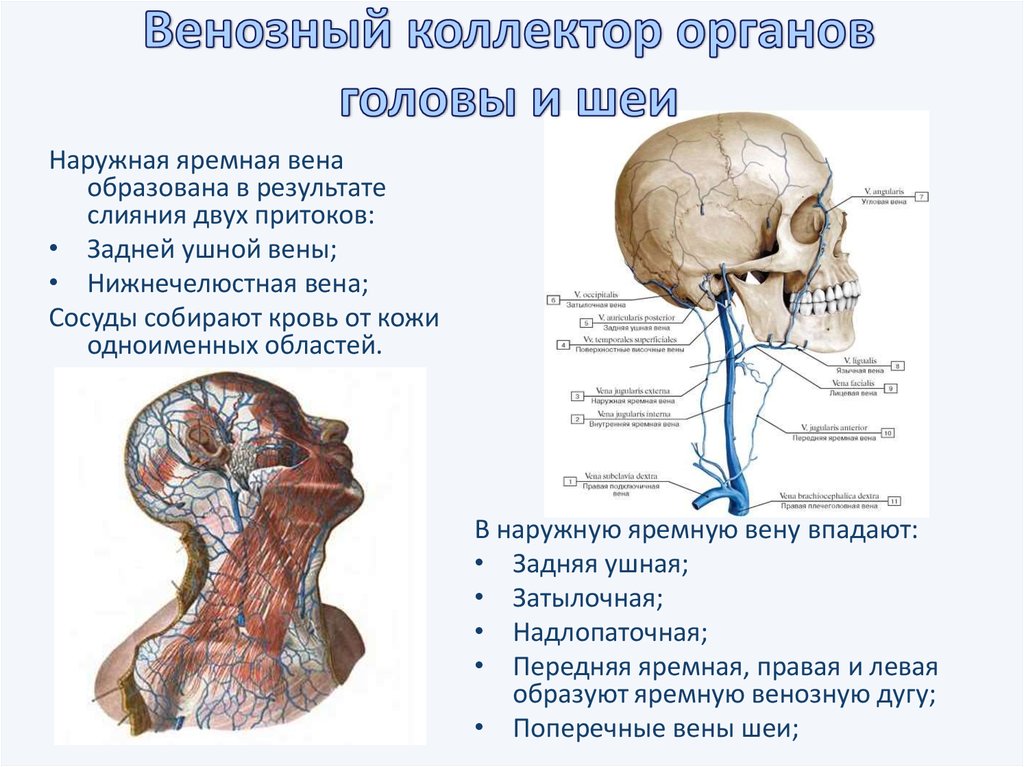

Анатомия внутренней яремной вены: КТ изображения